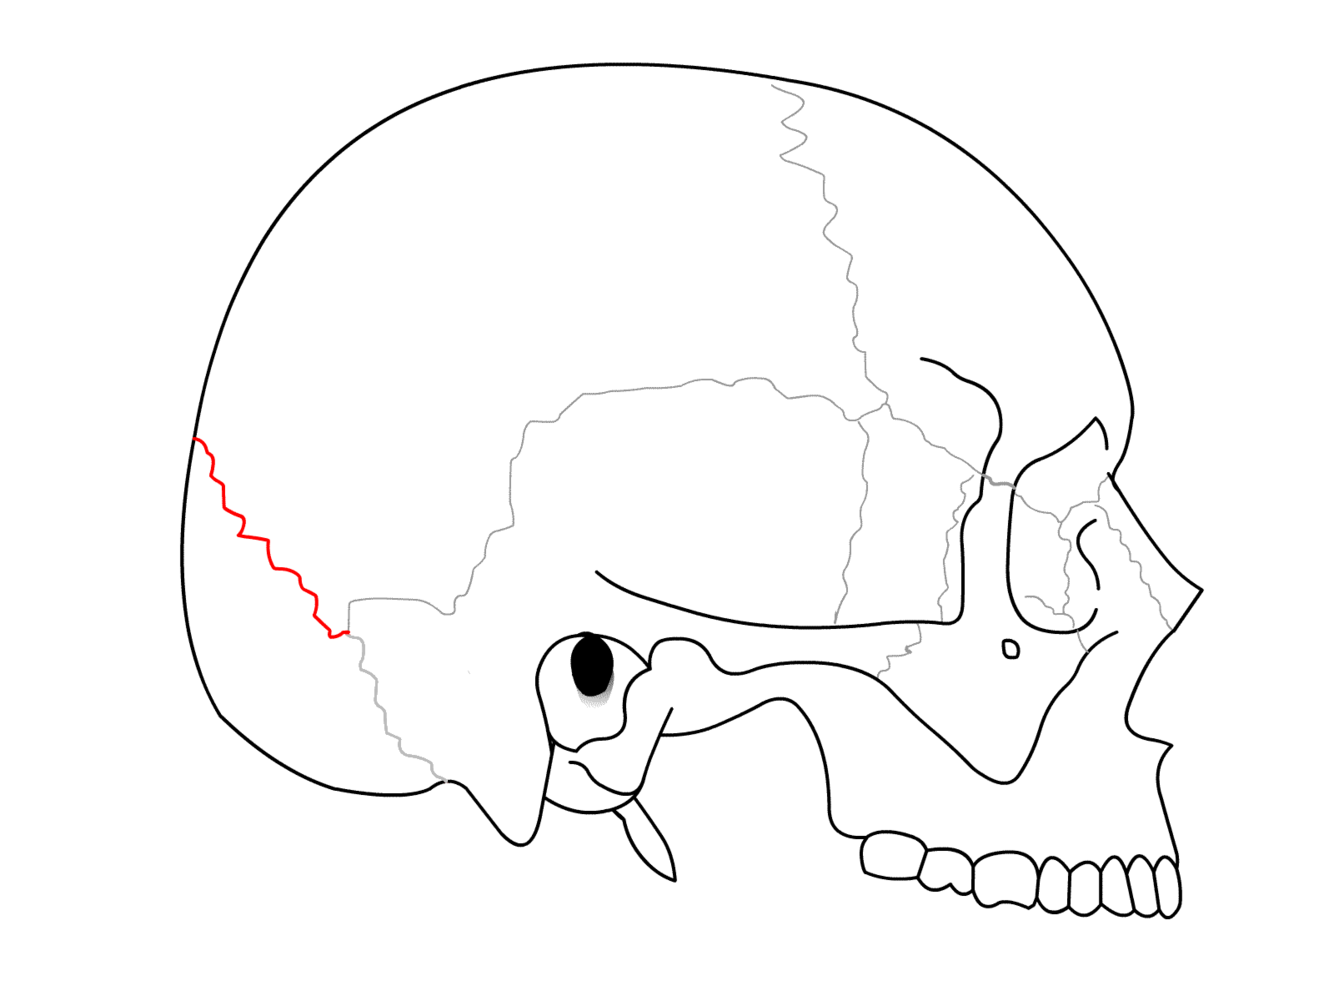

What suture is this?

Coronal suture

Sagittal suture

Lambdoid suture (parieto-occipital suture)